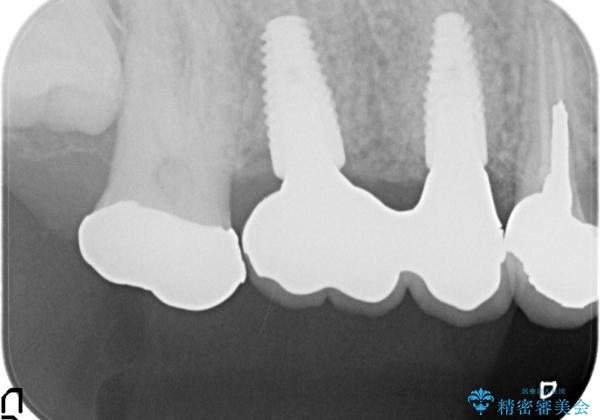

右上の567ブリッジを外したところ、右上5は歯根破折により保存不可能だったため、右上56部にインプラントを埋入し欠損補綴を行いました。

また右上5部に関しては抜歯時に歯槽堤保存術(抜歯窩に人工骨の填入を行う手術)を行い、骨の欠損を最小限に止めています。

- オールセラミッククラウン…¥100,000×2、仮歯…¥10,000×2、歯槽堤保存術…¥100,000、インプラント(ストローマン)…¥200,000×2、カスタムアバット…¥100,000×2費用は治療当時の料金となります